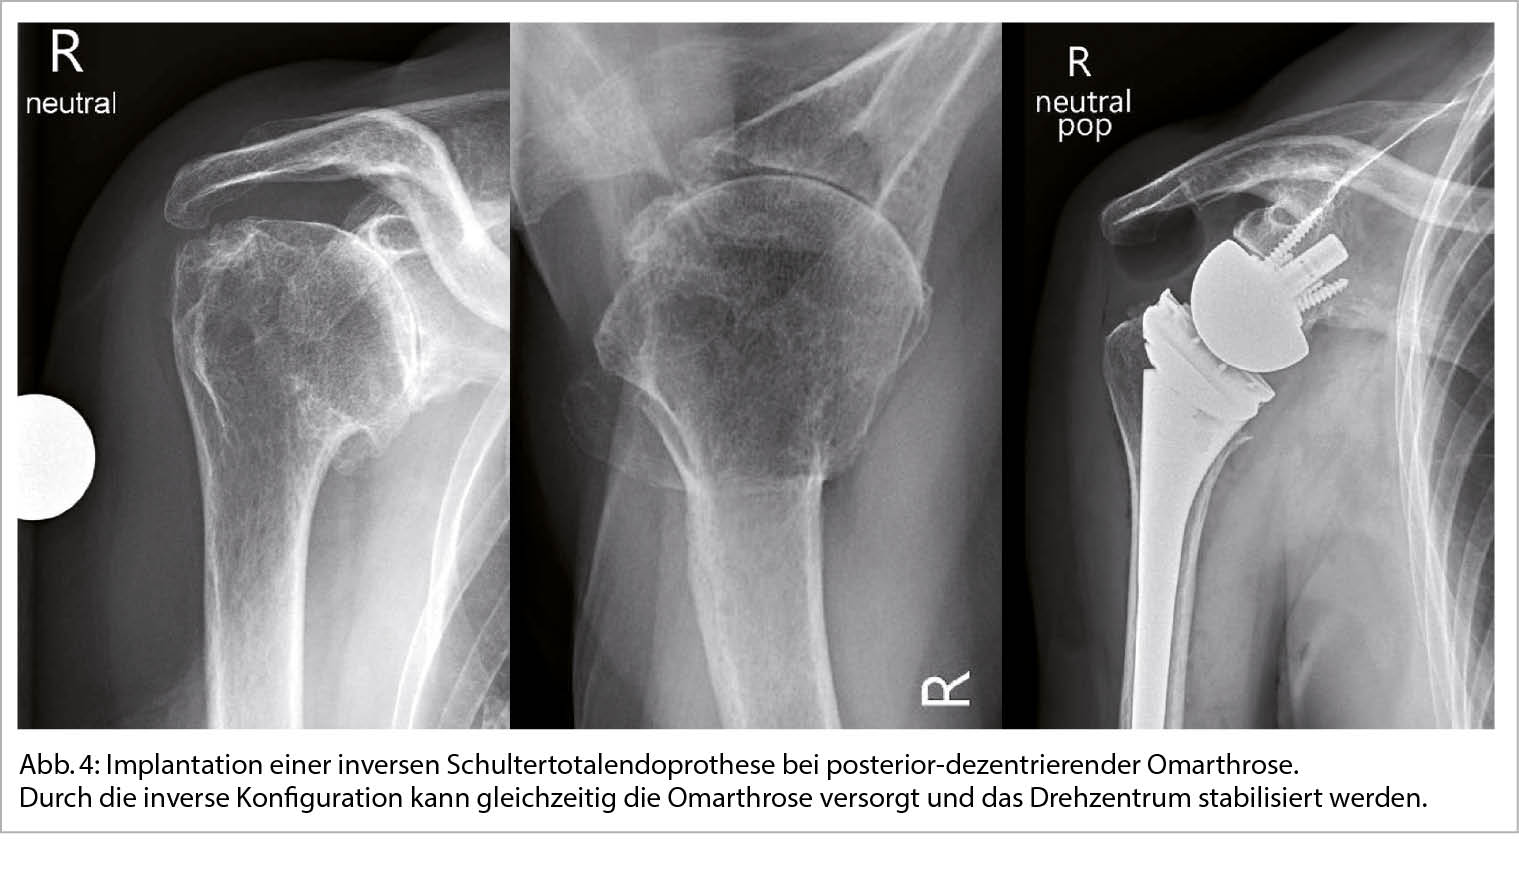

Die sekundäre GHA entstehen auf Basis einer klar definierten Ursache wie z.B. einer Gelenksinstabilität, Fehlstellung nach Trauma, oder einer medikamenteninduzierten Nekrose (Abb. 2).

Tritt eine primäre Arthrose frühzeitig auf, so sollte nach einer versteckten Ursache geforscht werden. Kürzlich konnten wir z.B. in einer Studie zeigen, dass häufig vergleichsweise junge Männer betroffen sind, die Sportarten mit einer hohen Belastung der Schultergelenke ausüben wie z.B. Kraftsport und Kampfsport. Vermeintlich kann eine repetitive Überlastung und ein unausgeglichenes Training zu einer Dysbalance der schulterstabilisierenden Kräftepaare führen und in weiterer Folge eine posterior-exzentrische Arthrose begünstigen (3).